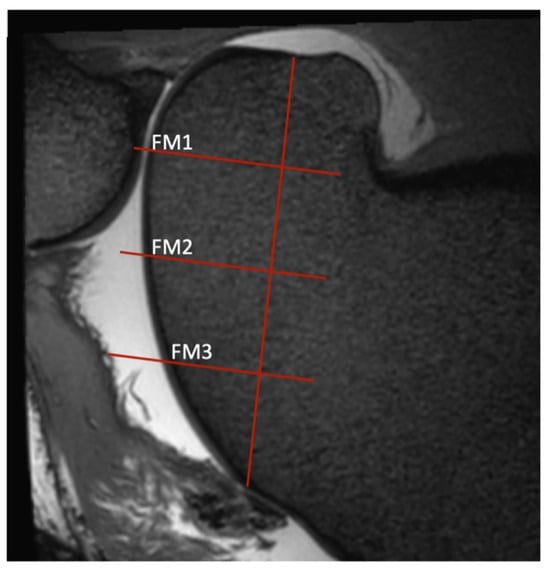

Figure 2. Sagittal view of a T2-weighted image of the medial trochlear ridge of a stifle, as determined by the procedure described in Figure 1. Three regions of interest (ROIs) were defined. In the sagittal view, a line was drawn from the notch where the trochlea ends and the condyle starts up to where the trochlear cartilage ends. This stretch was then quartered, resulting in three lines perpendicular to the original line. Where these lines intersect with the articular cartilage, ROIs (FM1, FM2, and FM3) were determined and the cartilage thickness was measured. The same process was repeated for the lateral dorsal view in the respective sagittal planes. For the lateral measurements, the middle of the origin of the lateral digital extensor tendon was used as the starting point of the vertical line and the proximal edge of the cartilage as the end. For the trochlear groove, the distal and proximal cartilage edges were used as starting and end points. As on the medial trochlear ridge, these two lines through the lateral trochlear ridge and the central groove were quartered with lines perpendicular to the first, resulting in three ROIs each.